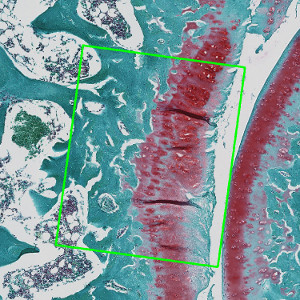

Coronal histological section of guinea pig knee joint, stained with Safranin O and Fast Green. Analysis box placed at the medial tibia cartilage.

Closeup on medial tibia cartilage with Analysis box.